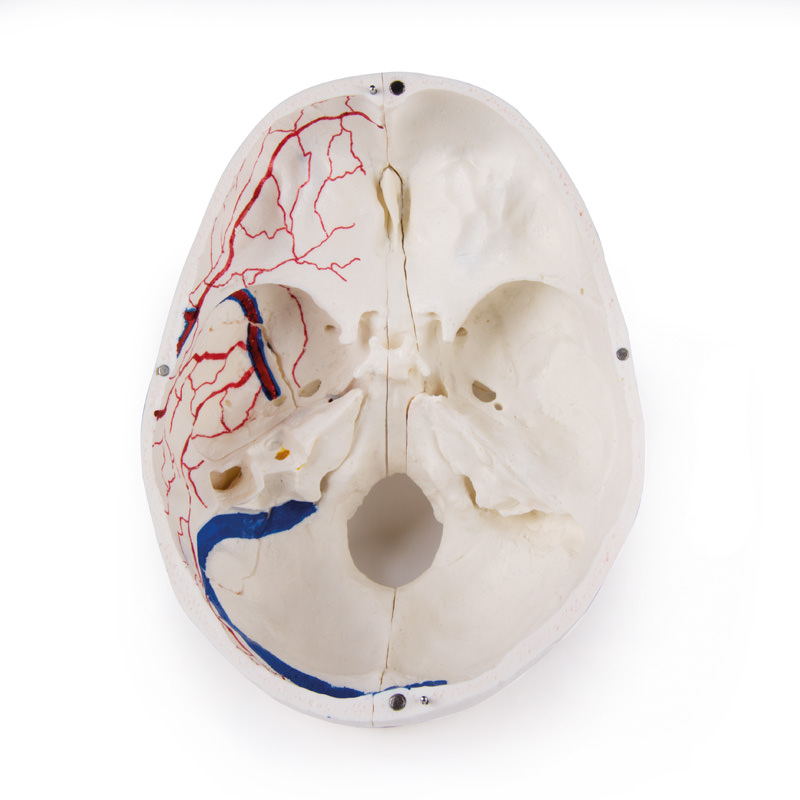

Das Schädeldach ist eröffnet und abnehmbar lässt aber die Schläfenbeine und ihre Nähte unberührt. Knöcherne Impressionen des sinus sagittalis, des sinus transversus und des sinus sigmoideus wie auch der Hirnhautgefäße sind bemalt. Die Schädelbasis ist sagittal geschnitten in der Form, dass der Schnitt auf einer Seite durch eine Siebplatte und ein weiterer Schnitt mit gleicher Ebene durch die andere Siebplatte des Siebbeins verläuft, was die Christa galli und die Lamina perpendicularis wie auch die ganze Nasenscheidewand intakt lässt. Die Strukturen der vorderen, mittleren und hinteren Schädelgrube sind einfach zugänglich. Man kann direkt die Nasenhöhle, die Nasenmuschel, das Septum sowie den knöchernen Rachenraum und Nasenrachenraum sehen. Die Nasenscheidewand kann aus den umgebenden Knochenstrukturen entnommen werden. Die Stirnhöhlen sind auf der einen Seite als Ganzes präpariert, auf der anderen Seite eröffnet, so dass sie voll zugänglich ist. Die Beziehung dieses Sinus zur Nasenhöhle ist klar zu erkennen, dies ist besonders wertvoll für HNO-Ärzte.